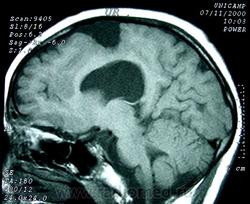

ГМ. Шизэнцефалия. +

Шизэнцефалия характеризуется расщеплением коры головного мозга линеинои формы, которое распространяется от желудочков к субарахноидальному пространству. Предположительно возникновение шизэнцефалии связано с окклюзией средних мозговых артерий, что может объяснить двусторонний характер поражения. В случаях шизэнцефалии нарушение сосудистого питания приводит не столько к разрушению мозговой ткани, сколько к ее неправильному формированию. Сочетание шизэнцефалии с другими аномалиями развития мозга свидетельствует о наличии другого механизма ее возникновения - первичных нарушений в большая часть коры разрушается. Многие из выживших детей страдают тяжелой умственной отсталостью.

Основным диагностическим критерием шизэнцефалии является наличие двусторонних дефектов, исходящих из боковых желудочков в направлении к наружной поверхности коры головного мозга. Обычно дефекты располагаются симметрично, хотя могут быть и односторонними.

Отдел патологии, школа медицинских наук.

Государственного Университета Кампинас (UNICAMP).

Кампинас, Сан-Паулу, Бразилия.